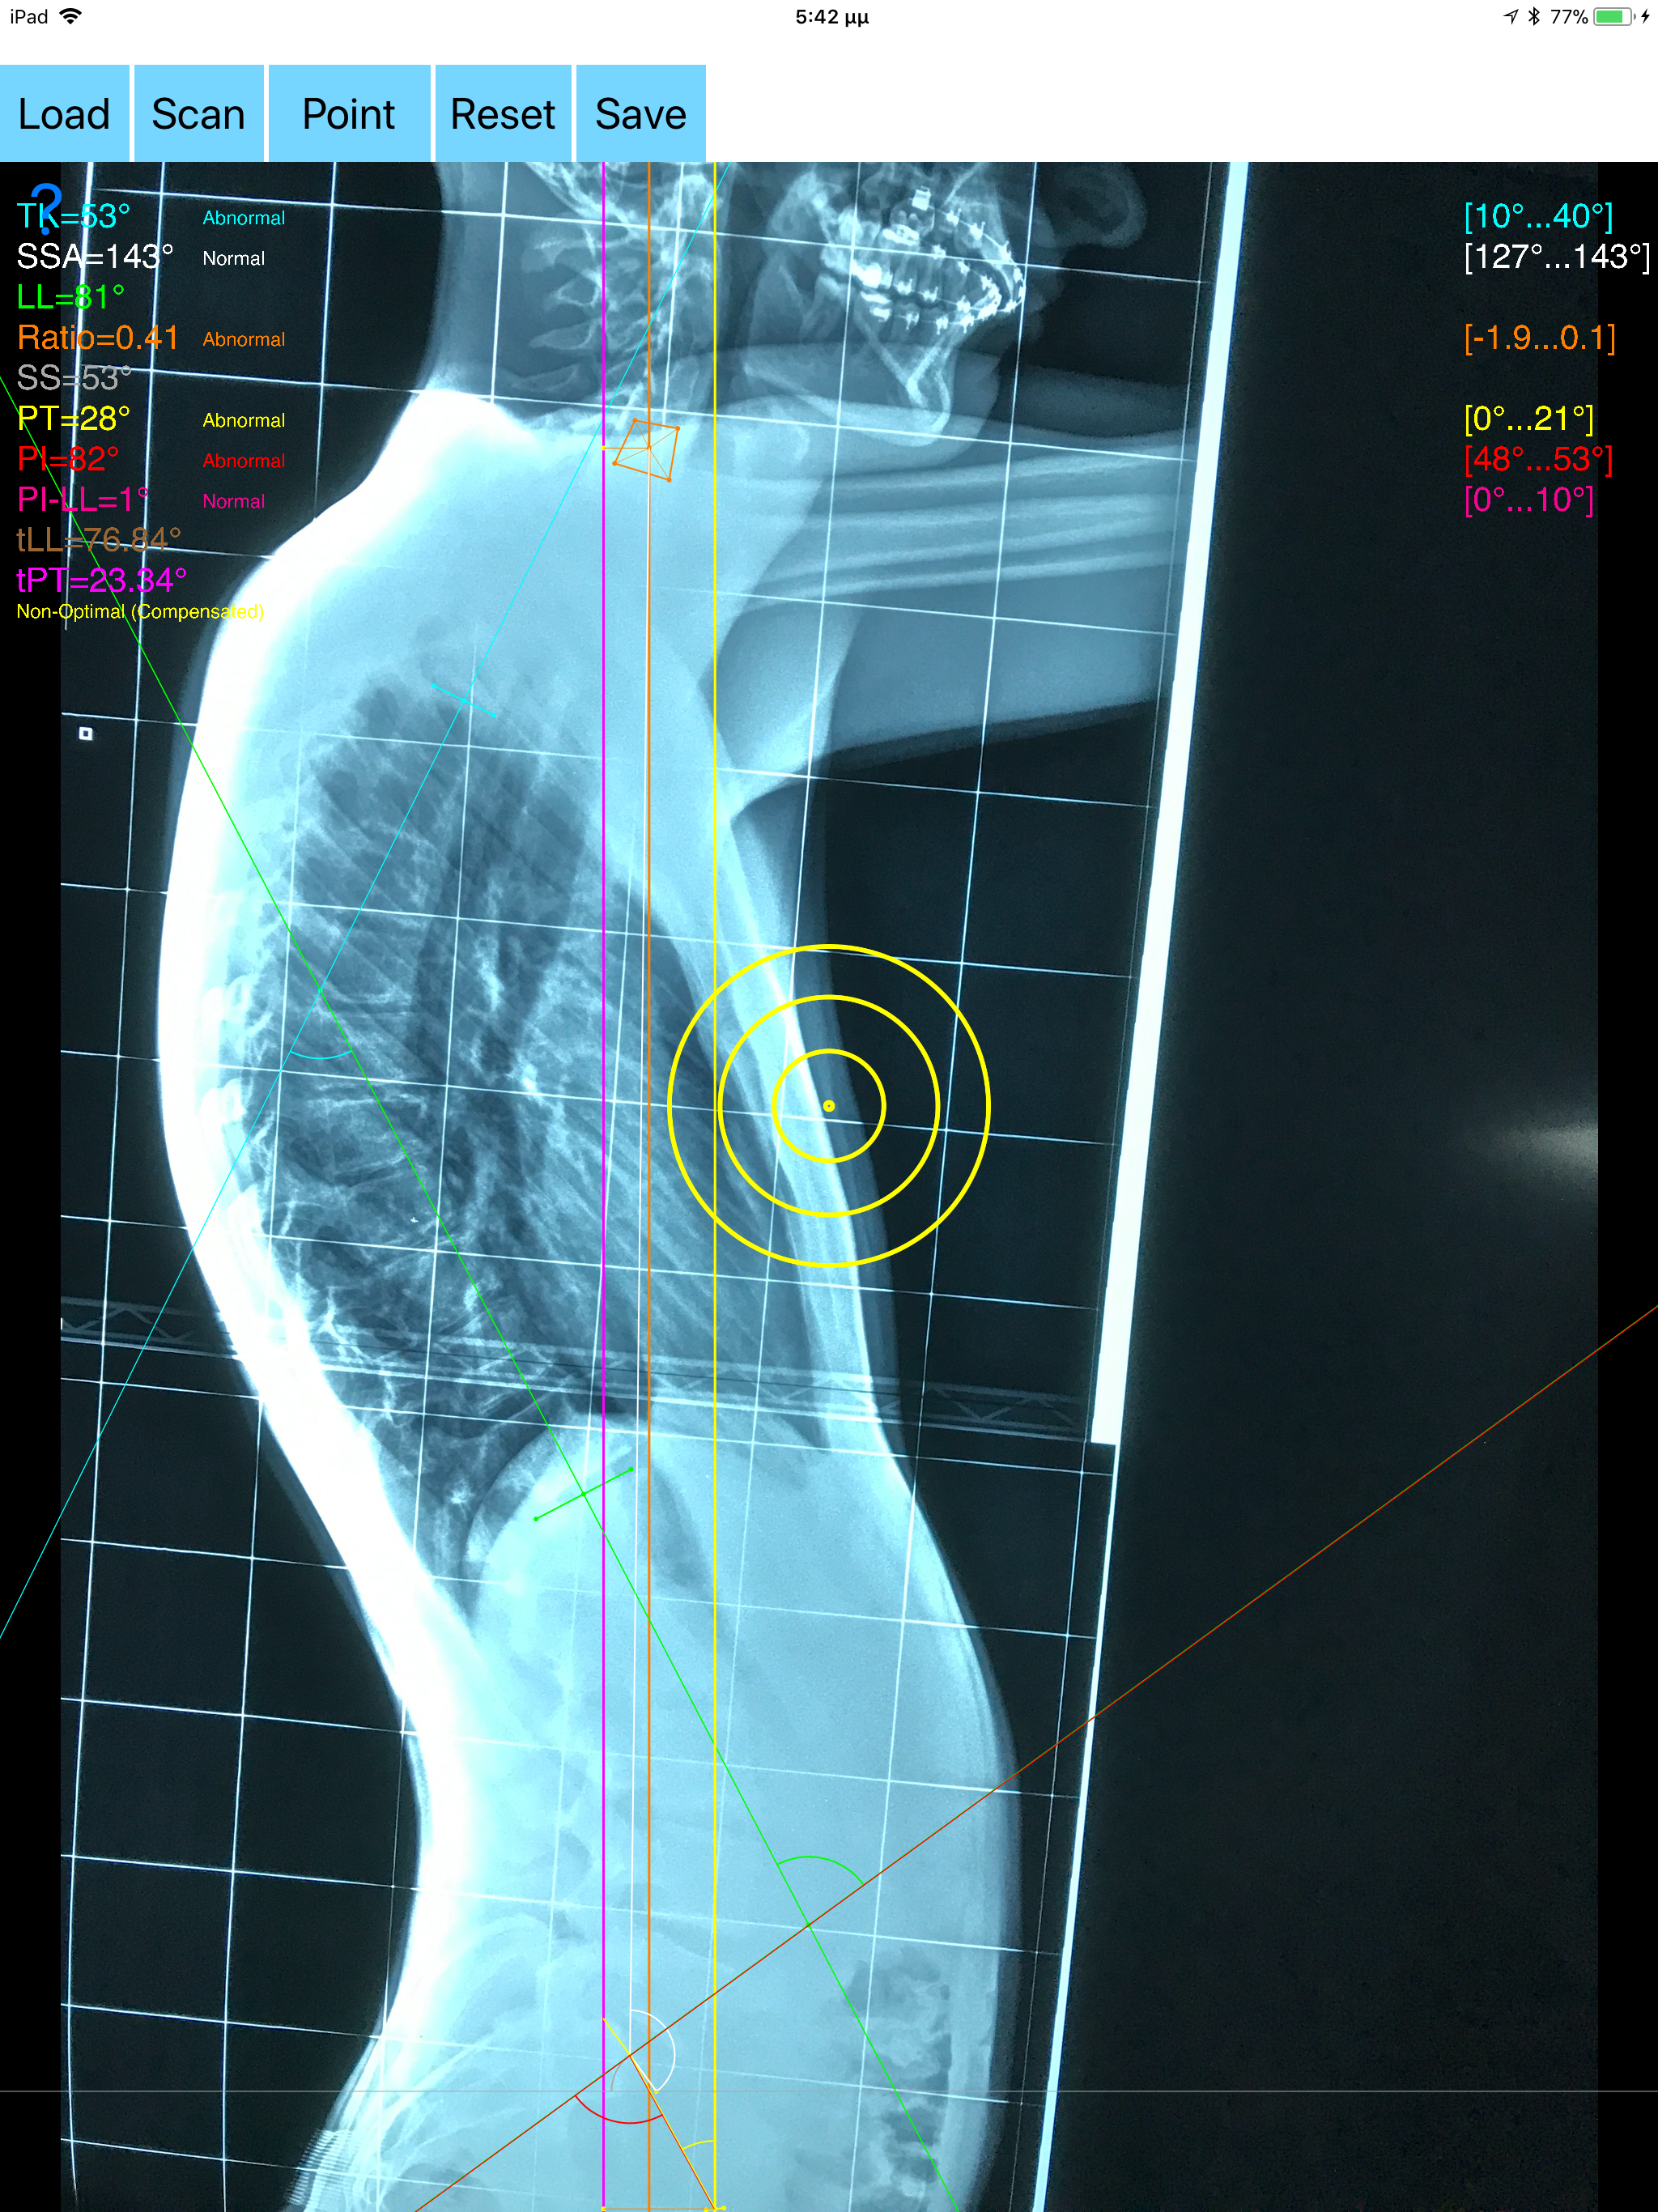

The assessment of global sagittal alignment and the compensatory mechanisms which are implicated in the spine and the spinopelvic jucture are of paramount importance for spine and joint replacement surgeon. The dynamic interplay between flexibility and balance around the axis of gravity determine the type and the amount of influence in spine and hips. Radiographic parameters to evaluate objectively the sagittal balance are Pelvic incidence (PI), Sacral slope (SS), Pelvic Tilt (PT), Lumbar lordosis (LL),Thoracic Kyphosis, C7 plumb line (C7PL) and its ratio. Drawings in patients X-rays and precise measurements are important in order to quantify the magnitude of spinal deformities, to monitor the success or failure of treatment and thus optimise the management of patients according to the severity of the imbalance. The Sagittal Balance App is medical software aimed for orthopaedic surgeons, providing tools that allow doctors to: -Securely import medical images directly from the camera or stored photos. -By marking several points at the image of X-ray, the App calculates and offers a very convenient way to determine the most accurate possibly way at once, Pelvic incidence (PI), Sacral slope (SS), Pelvic Tilt (PT), Lumbar lordosis (LL), thoracic kyphosis, C7 plumb line (C7PL), C7PLD/sfd ratio, PI–LL, theoretical normal pelvic tilt (tPT),theoretical normal L1-S1 lumbar lordosis (tL1S1), Spino-sacral angle (SSA) According to measured parameters the app categorizes the severity of the imbalance of spine, in three different stages: optimal balanced, balanced with compensatory mechanisms and imbalanced. -Save the planned images, for later review or consultation.The measured values are compared by normal reference databases and also data are exported as txt file, ready to print or to input as cells to excel for research. -The app also allows the calculations of centroids after choosing points in vertebra body in independent manner from order. All information received from the software output must be clinically reviewed regarding its plausibility before patient treatment! Sagittal Balance App indicated for assisting healthcare professionals. Clinical judgment and experience are required to properly use the software. The software is not for primary image interpretation. In a busy everyday practice, the examiner have to draw lines in X-rays or in clinical settings, this it is time consuming and cumbersome. Accessory instruments like protractors, hinged goniometers, well sharped pencils, rulers or even transparent papers must be available. The app offers a very convenient and accurate way to perform most common radiographic measurements for spine, and spinopelvic juncture in a blink of an eye in front of your screen. The build in feature of the app, allows results to be categorized may help decide what could be considered normal or pathologic. The app is not a simple goniometer, is an enhanced product which helps to monitor objectively the course of the treatment and evaluate optimally the spine. This App is particular useful especially in clinical settings where you need a quick results without losing time. Please see tutorial videos at the developer’s web site www.orthopractis.com Reference databases 1.Legaye J, Duval-Beaupe`re G, Hecquet J, Marty C (1998) Pelvic incidence: a fundamental pelvic parameter for three-dimensional regulation of spinal sagittal curves. Eur Spine J 7(2):99–103 2. Cavanilles-Walker JM, Ballestero C, Iborra M, Ubierna MT, Tomasi SO (2014). "Adult Spinal Deformity: Sagittal Imbalance". International Journal of Orthopaedics.